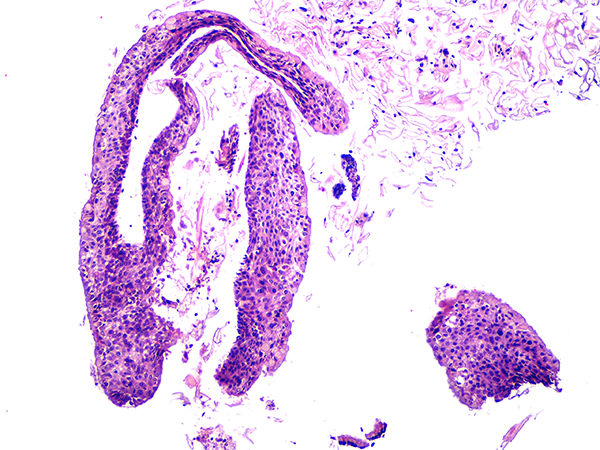

![]() Case 2

Soft Bx CIN 2 10x - Low Power |